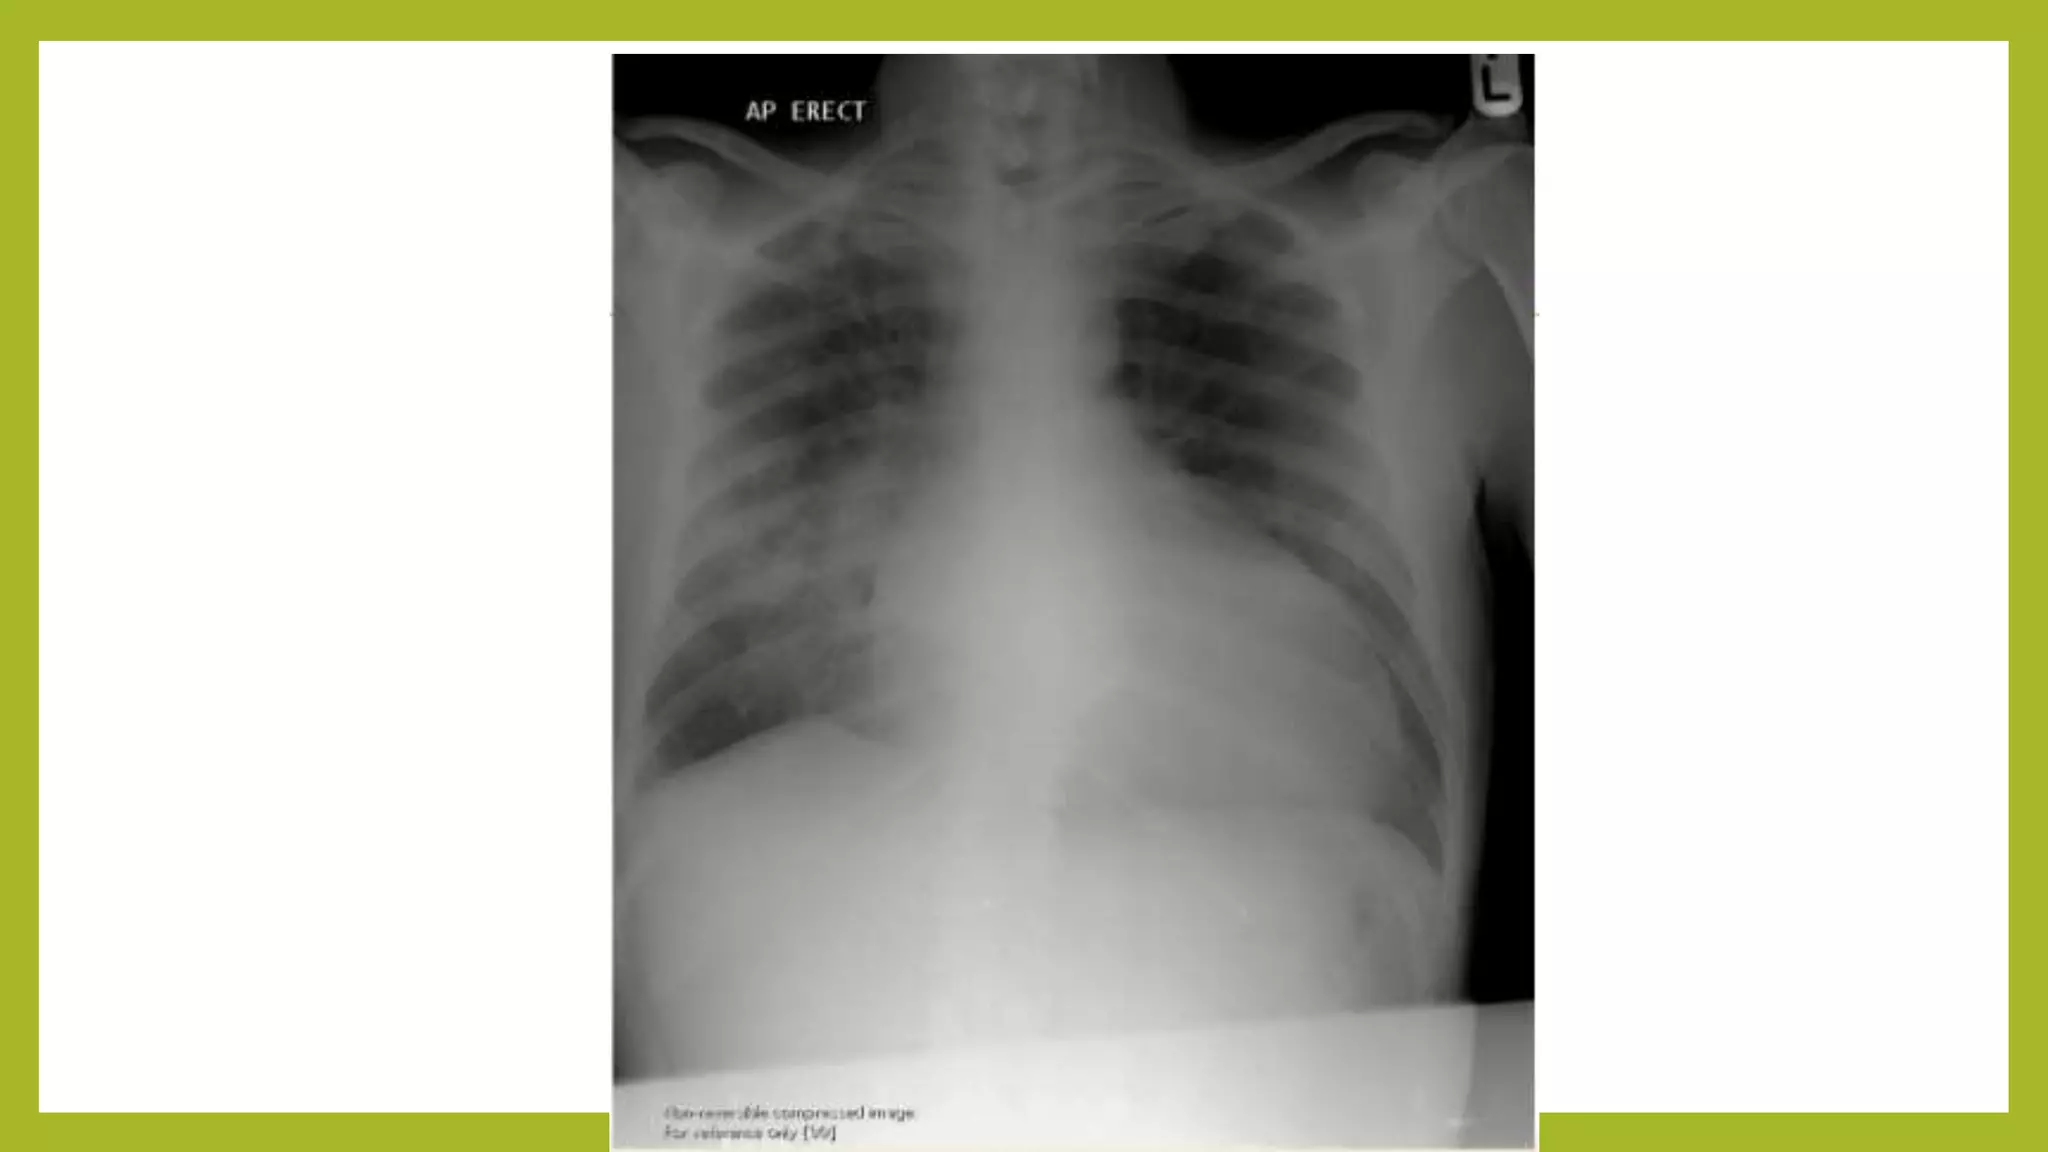

The document provides guidance on approaching and interpreting chest x-rays (CXR). It outlines steps to check the name, date and quality of the film, systematically scan the CXR looking for abnormalities, and determine if the lungs appear too white or black. Specific signs are described to help localize abnormalities, including the cardiac silhouette sign and pleural effusion signs. Examples are given of respiratory distress syndrome, tetralogy of fallot, transposition of great arteries, and total anomalous pulmonary venous return. The take home message is to summarize positive findings, compare to prior CXRs if available, and confirm findings with a radiologist.